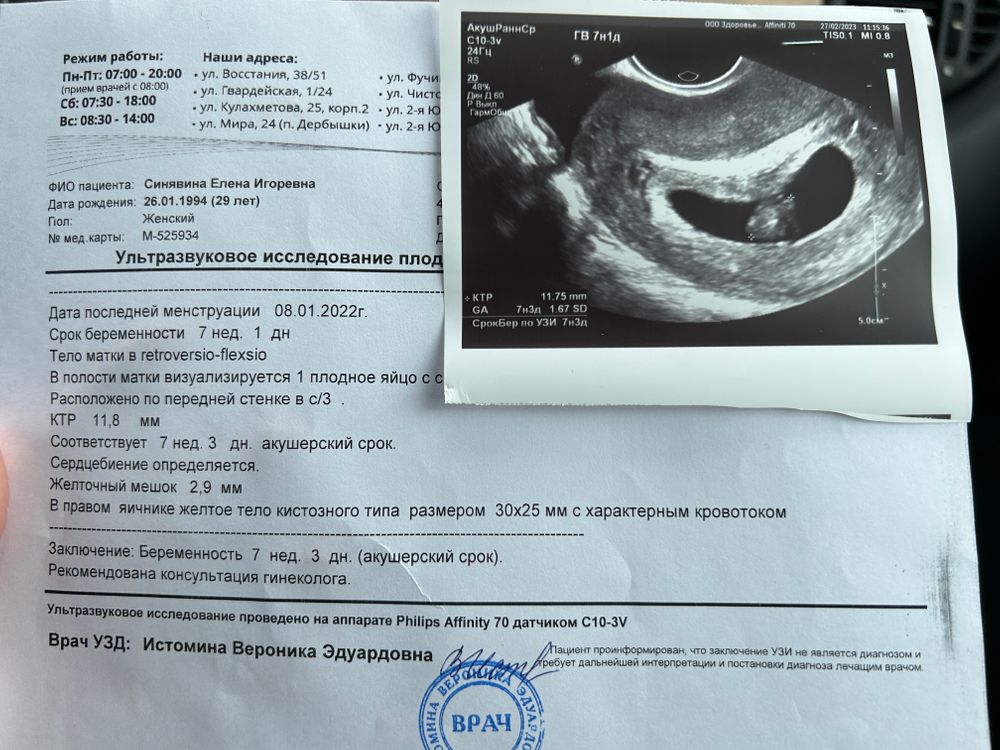

УЗИ двухплодной беременности на 5 неделе: Подборка изображений

Раздел: Калейдоскоп образов